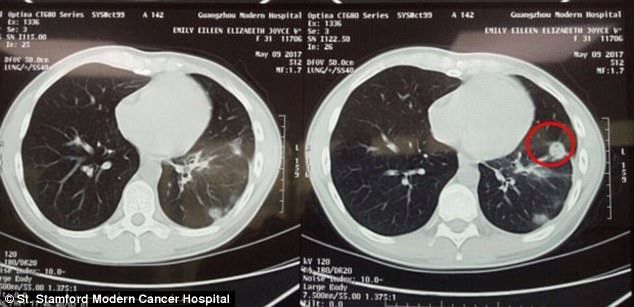

去医院后,她再一次收到了打击:肺部也有了肿瘤,7厘米左右。

没过多久,她体内的肿瘤就从7厘米缩减到了3厘米大小。